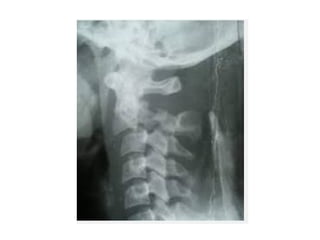

Rx SIMPLE DERx SIMPLE DE

COLUMNA CERVICALCOLUMNA CERVICAL

VISTA LATERALVISTA LATERAL

Imágenes

Aplastamiento vertebral

Osteofitos

OSTEOPOROSIS.